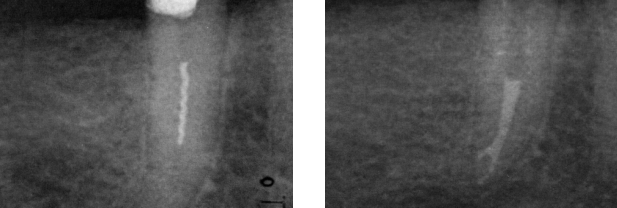

Снимок определения рабочей длины. Виден ByPass сломанного

инструмента.

Снимок наблюдения через 6

месяцев. Практически полное исчезновение периапикальных процессов на М и Д

корнях